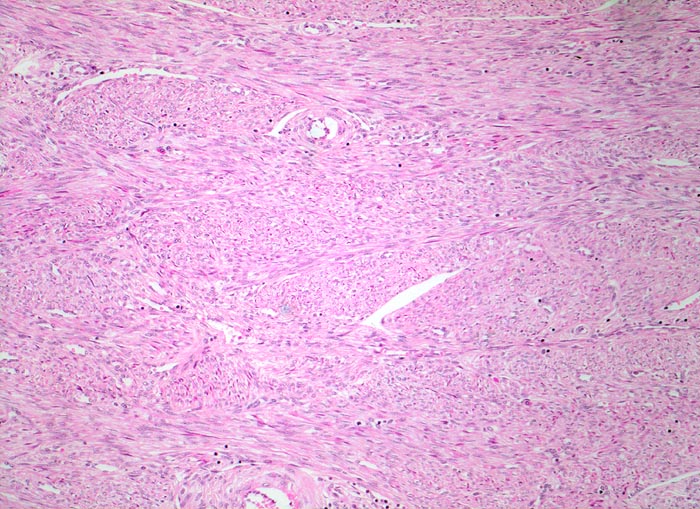

Morphologische Merkmale:

• Zwei scharf begrenzte Knoten im Myometrium bestehend aus Bündeln glatter Muskulatur.

• Variabler Anteil Fibrose (Kollagenfasern).

• Glatte Muskelzelle: eosinophiles Zytoplasma, längliche Kerne mit abgerundeten Enden (zigarrenförmig).

• Keine signifikanten Zellatypien. (signifikant=bereits in der Übersichtsvergrösserung erkennbar).

• Keine Mitosen.

• Keine Tumornekrosen.

• Das Endometrium über dem Leiomyom ist druckatroph, das übrige Endometrium zeigt Proliferationszeichen.